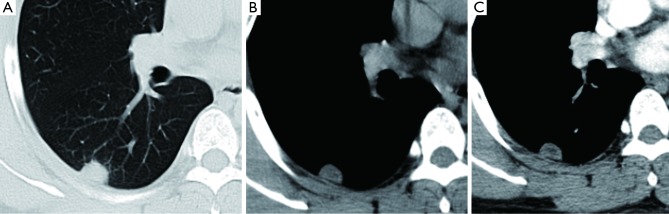

Figure 8.

(A) CT shows a SPN (arrow, size =14 mm × 18 mm) in a 73 yrs male; (B) the same patient follow-up CT scan 20 month later. The size increased to 20 mm × 33 mm, with typical malignant the appearance of lobular contour and spiculated margin, and pathologically proved to be adenocarcinoma.